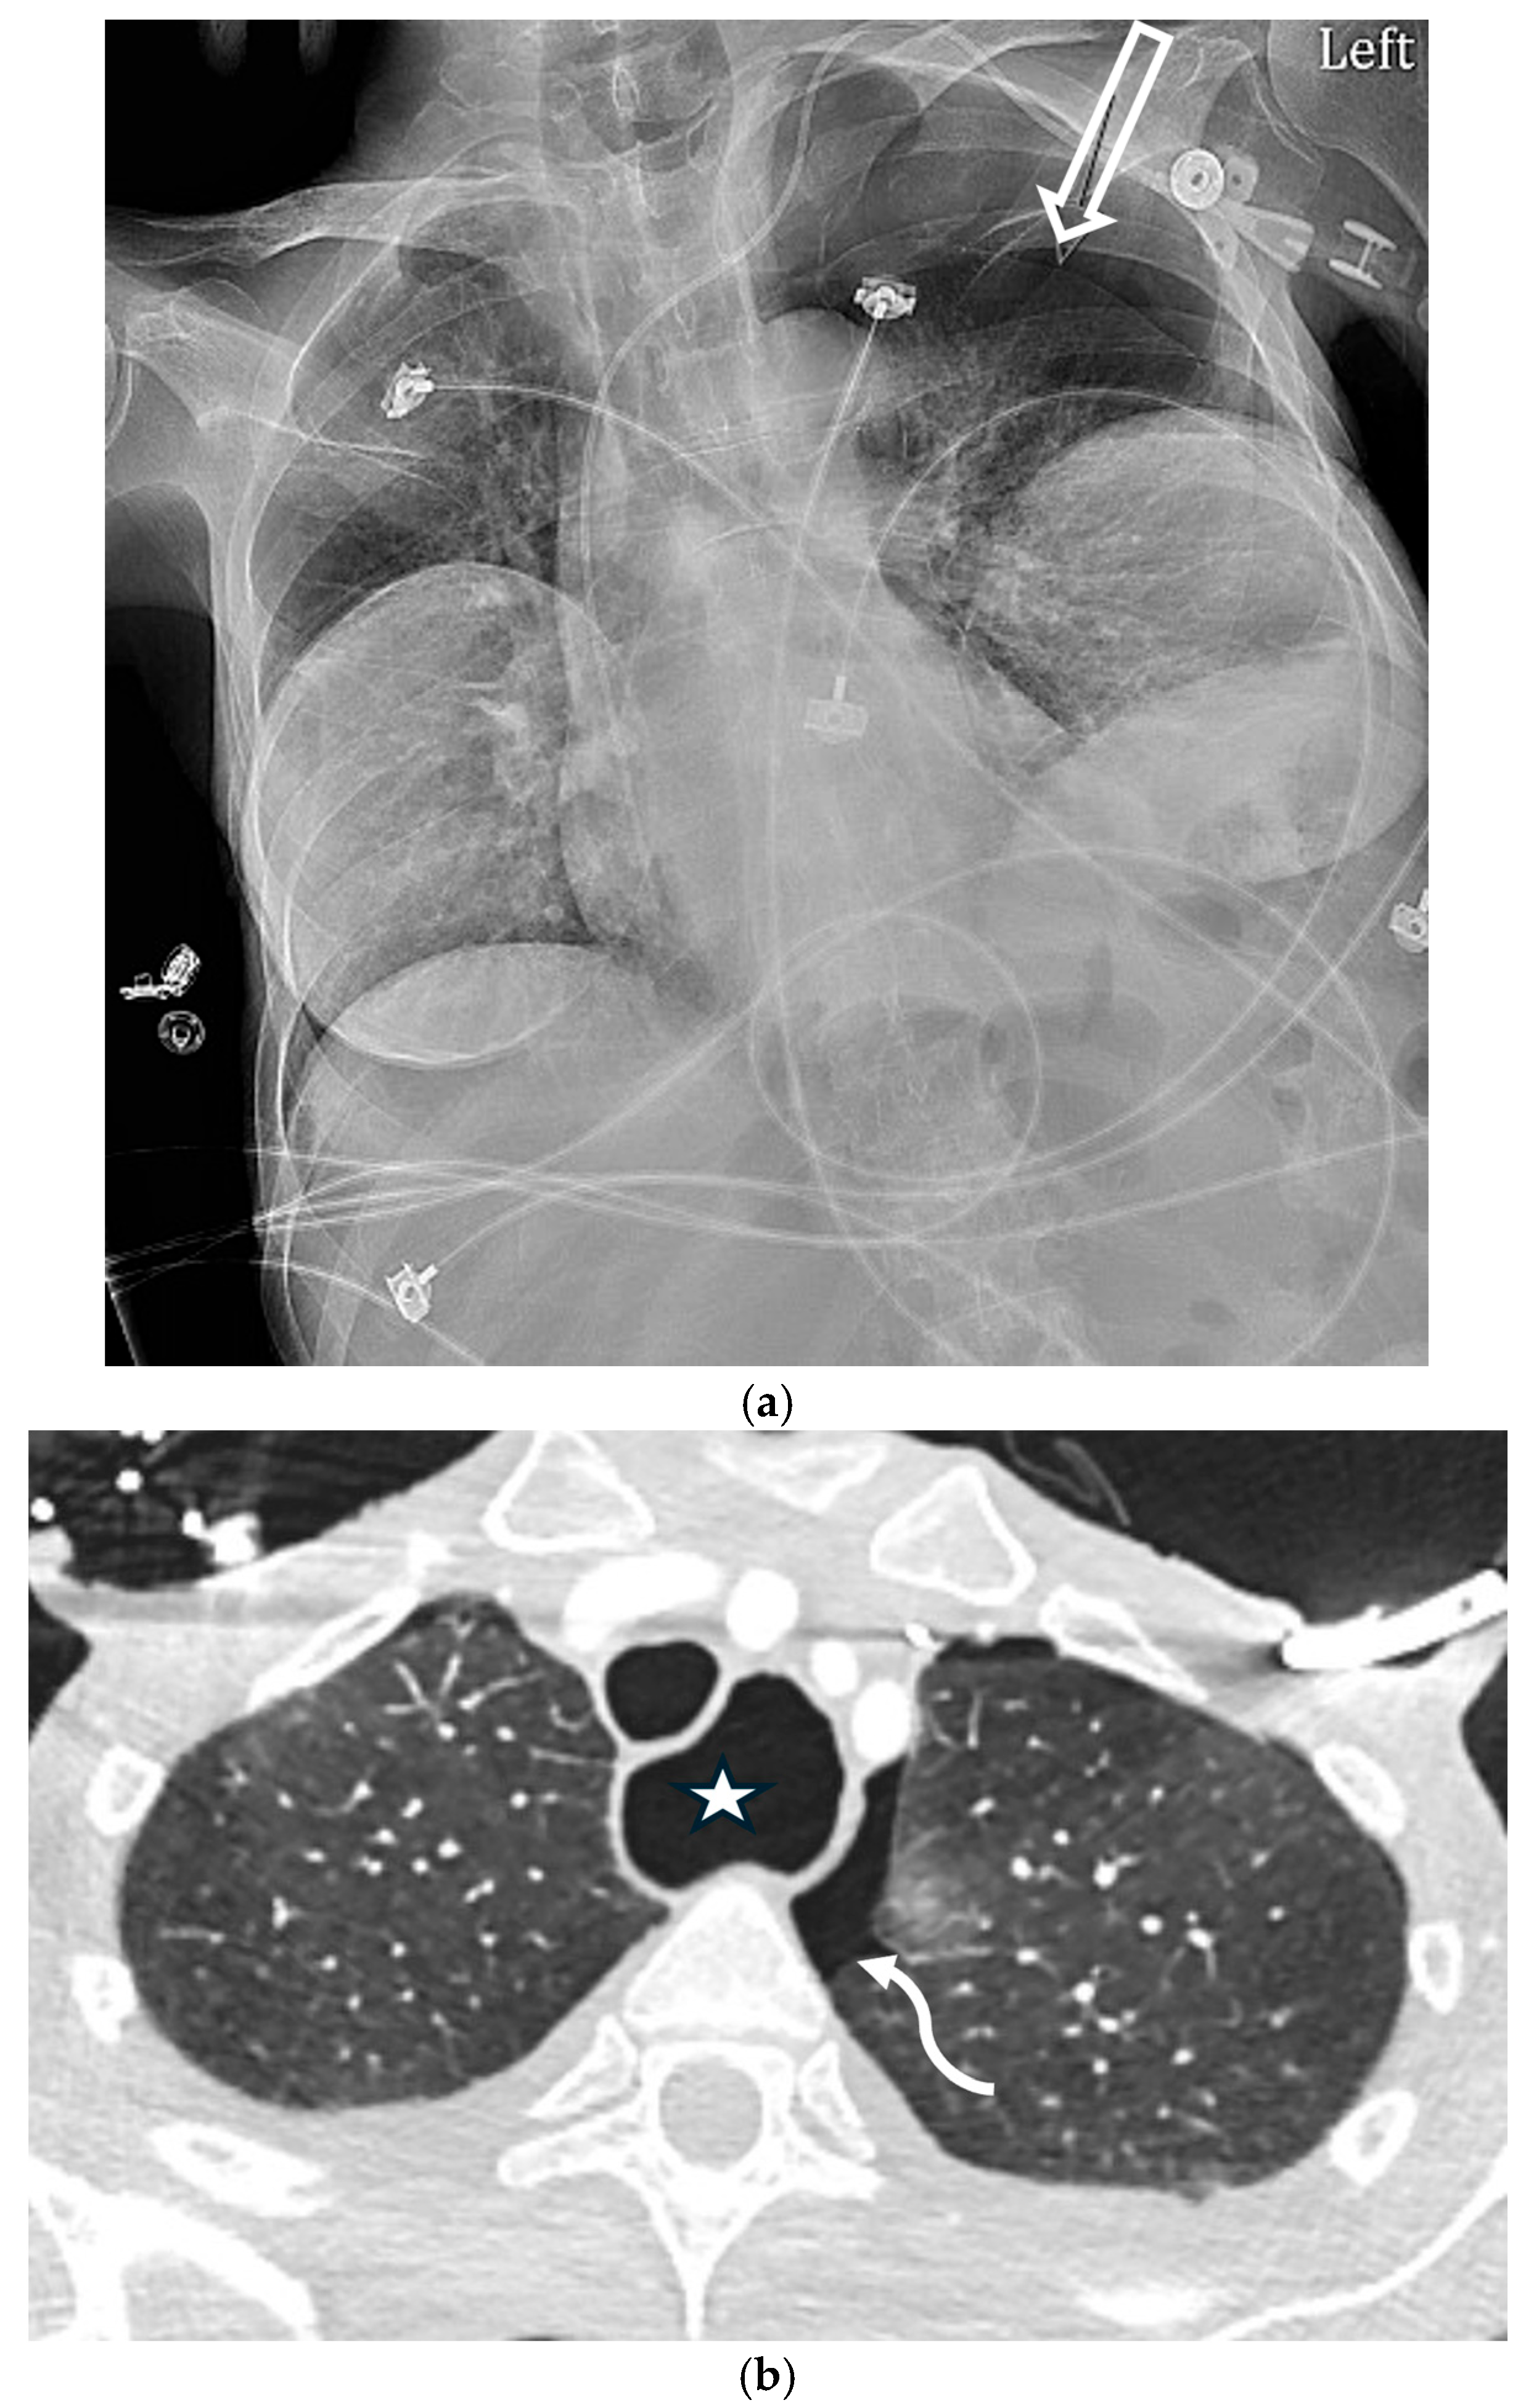

5.1.2. COVID-19 Pneumonia

5.1.3. Pneumocystis jirovecii Pneumonia (PJP)